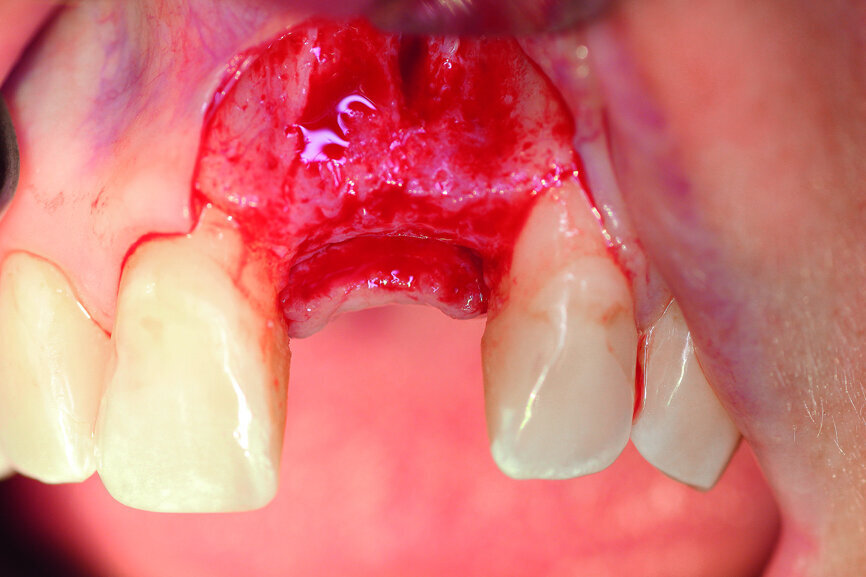

A 40-year-old female patient presented to our dental surgery with an irreparable tooth #21 (Fig. 1). The periapical radiograph revealed an approximately 7 mm periapical translucency with widening of the periodontal ligament in the upper third of the root (Fig. 2). Owing to the clinical conditions (high smile line and good oral hygiene), we decided to use a two-piece ceramic implant, ZERAMEX XT (Dentalpoint).

Fig. 1: Initial clinical situation.

After extraction of tooth #21, the apical granulation tissue was excochleated through a semilunar incision (Fig. 3). A two-stage procedure was performed to prevent failure of osseointegration of the ceramic implant and to preserve the soft-tissue structures (papillae and attached gingiva). A claspless prosthesis made from Valplast (Valplast International) served as a temporary restoration. The implant site in region #21 was uncovered after five months (Fig. 4). A two-piece ceramic implant (diameter: 4.2 mm; length: 12.0 mm) was then inserted (Figs. 5a & b). The guidelines for implant placement in the aesthetic zone and the drilling procedure specified by the manufacturer were observed.13, 14 Both vertical and transverse insertion depth are decisive for prosthetic success. The implant can be placed between 1.6 mm and 0.6 mm supracrestally because of a special thermal etching procedure in the collar region; the insertion depth is determined by the gingival height and the existing bone of the adjacent teeth. The implant positioning should be approximately 2–3 mm subgingivally because the abutments are added 1 mm above implant shoulder level. Transversal bone augmentation was performed with a mixture of autogenous bone chips (retrieved from the retromolar mandible), xenograft (Geistlich Bio-Oss, Geistlich Biomaterials) and guided bone regeneration (Jason membrane, botiss biomaterials; Figs. 6a & b). The exposure was performed after four months using a PEEK gingiva former (Fig. 7).